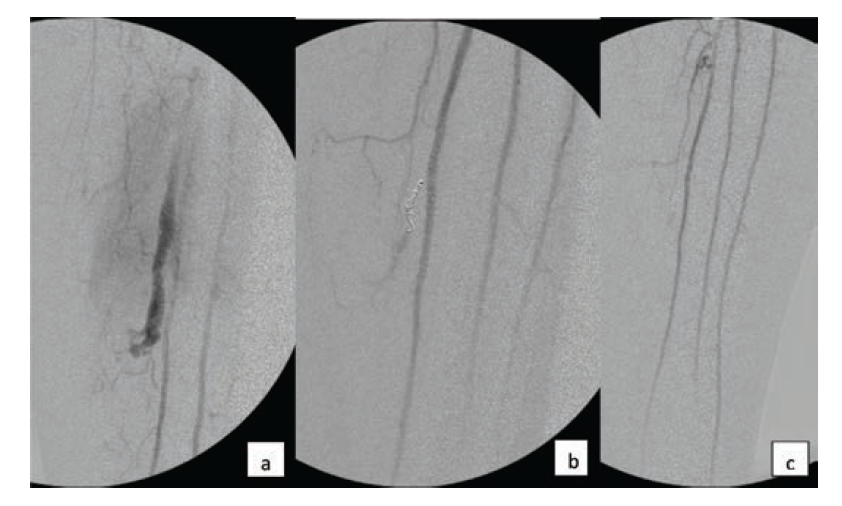

Atherectomy is commonly used in lower extremity endovascular procedures, both in the femoropopliteal and tibial vascular territories. There are many devices available with different mechanisms of action, but they all have the goal of plaque removal in common, which comes with an increased risk of vessel perforation, particularly when treating a CTO. Contained perforation can often be successfully treated with reversal of anticoagulation and prolonged balloon inflation. Development of an arteriovenous fistula is generally well tolerated. In the femoropopliteal segment, a covered stent may be utilized if there is a free perforation. In the tibial arteries, covered stent placement is not an available option. A free perforation in a tibial artery can quickly result in compartment syndrome if it is not expeditiously treated. The complication demonstrated in Figure 3 did not resolve despite reversal of anticoagulation and prolonged balloon inflation. It was successfully resolved with stent-supported coil embolization. Drug-eluting stent deployment was able to maintain vessel patency, while the coils provided good resolution of the extravasation.